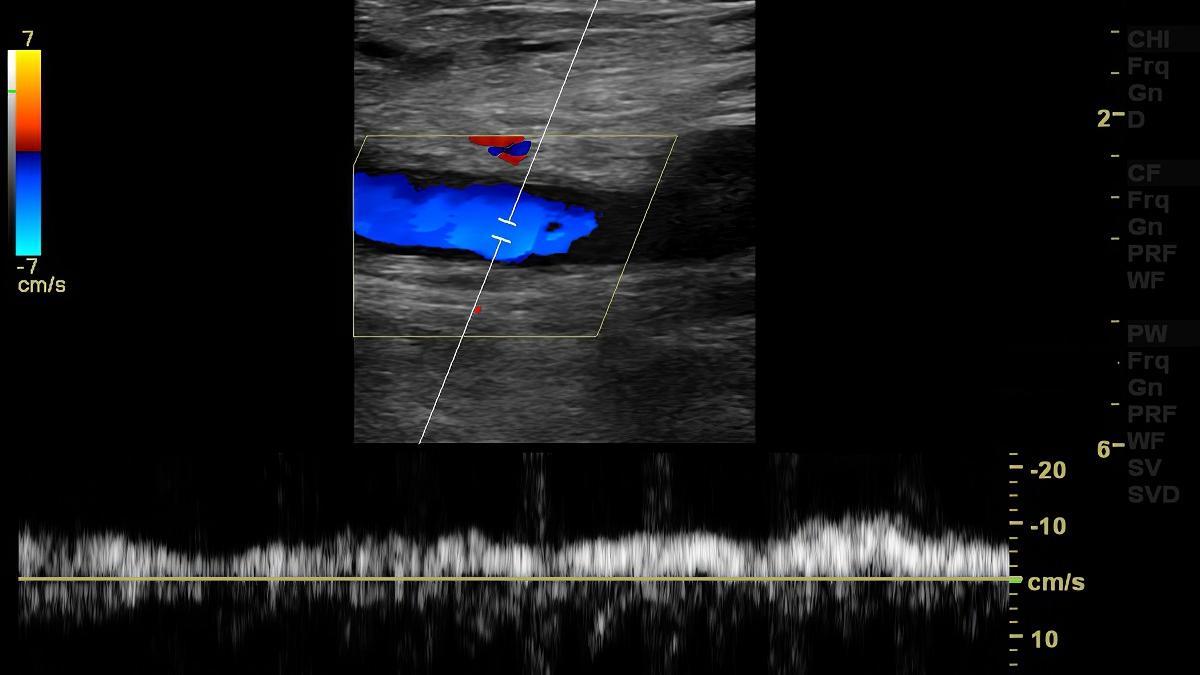

La trombosis consiste en la formación de un coágulo de sangre o trombo en el interior de un vaso sanguíneo, lo que puede obstruir el flujo normal de la sangre, y puede afectar a pacientes de cualquier edad, aunque el riesgo se incrementa a partir de los 40 años.